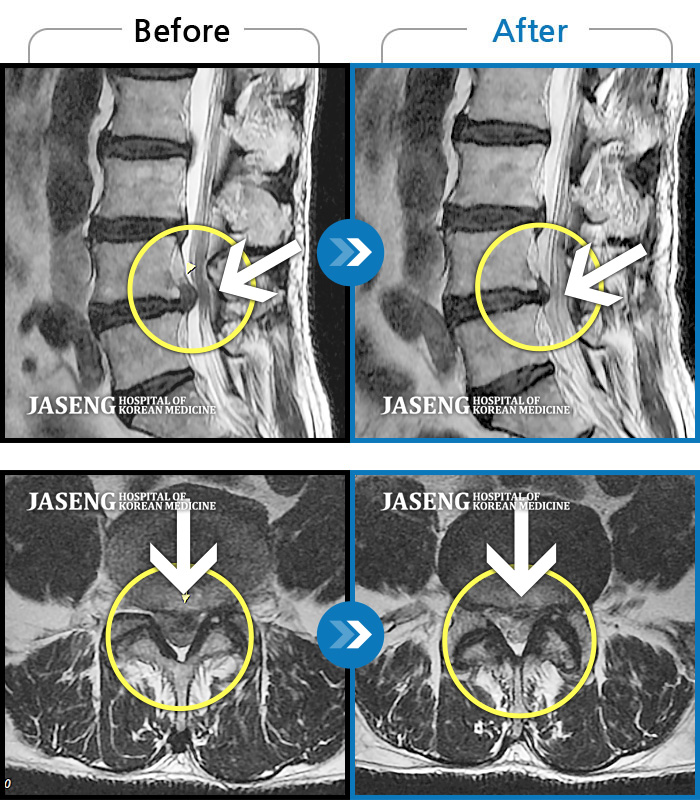

Before

After

환자에게 사전 동의를 받아 동일 조건에서 촬영되었습니다.

허리디스크로 연골이 거의 없다고 진단 받음

요통과 좌측 하지방사통으로 내원